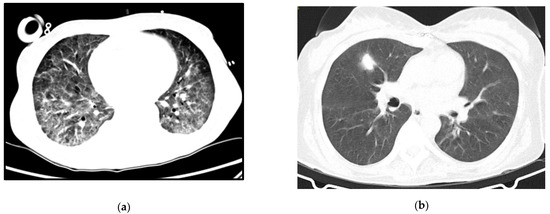

A 64-year-old woman with a history of hypertension, dyslipidemia and chronic pulmonary disease presented at the ER with fever, shortness of breath and a worsening cough despite a previous complete course of antibiotics for presumed CAP. She was hypoxic, with isolated elevation of CRP and diffuse ground-glass opacities on thoracic CT-scan (Figure 2a). Her status deteriorated despite antibiotics and oxygen supplementation in the Intermediate Care Unit, so she was transferred to the ICU and intubated. Three days after IMV and prone positioning, she was connected to VV-ECMO due to refractory respiratory acidemia. Anti-HIV testing was positive. Immune and viral study revealed severe immunosuppression (9 CD4+/mm3) and high serum viral load (4.050.000 copies/mL) and TMP-SMX plus corticosteroids were started for presumed PJP, at the recommended PJP treatment dosage. Diagnosis was confirmed by positive immunofluorescence for P. jirovecii in BAL.

Follow-up imaging can be seen in Figure 2b. She was transferred to a rehabilitation unit with a residual need of oxygen support (2 L per minute), from which she recovered after some months of pulmonary rehabilitation.

Figure 2. Case 2 thoracic CT-scan at diagnosis (a) and follow-up (b).